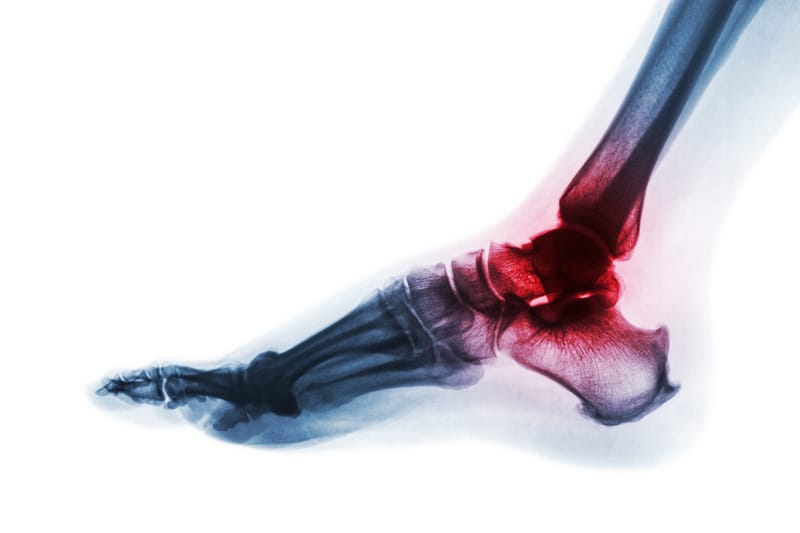

Quantum TAR with OrthoPlanify™, Patient Specific Instrumentation with software designed to provide complete visualization during case pre-planning, perform reconstruction and planning using CT scan and weight-bearing X-rays, as well as 3D-printed custom tibial and talar cutting and drilling guides.